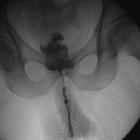

Enterocutaneous fistula

An enterocutaneous fistula is an abnormal connection between a loop of bowel and the skin. They occur most commonly secondary to abdominal surgery. Other less common etiologies are chronic inflammatory bowel diseases, tumors, and radiation enteritis.

Radiographic features